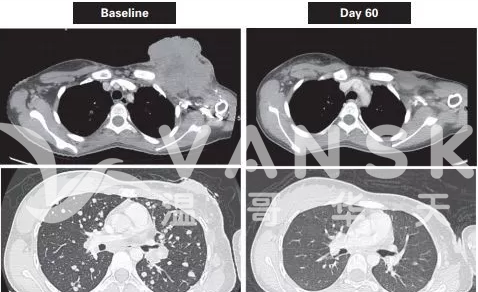

乳腺癌:

50岁女性

治疗前:这位患者之前接受过多次的化疗和手术治疗,无奈最后肿瘤还是复发了,情况很严重

治疗后:使用了抗癌药Vitrakvi治疗20天之后,裸露的肿瘤几乎消失了。